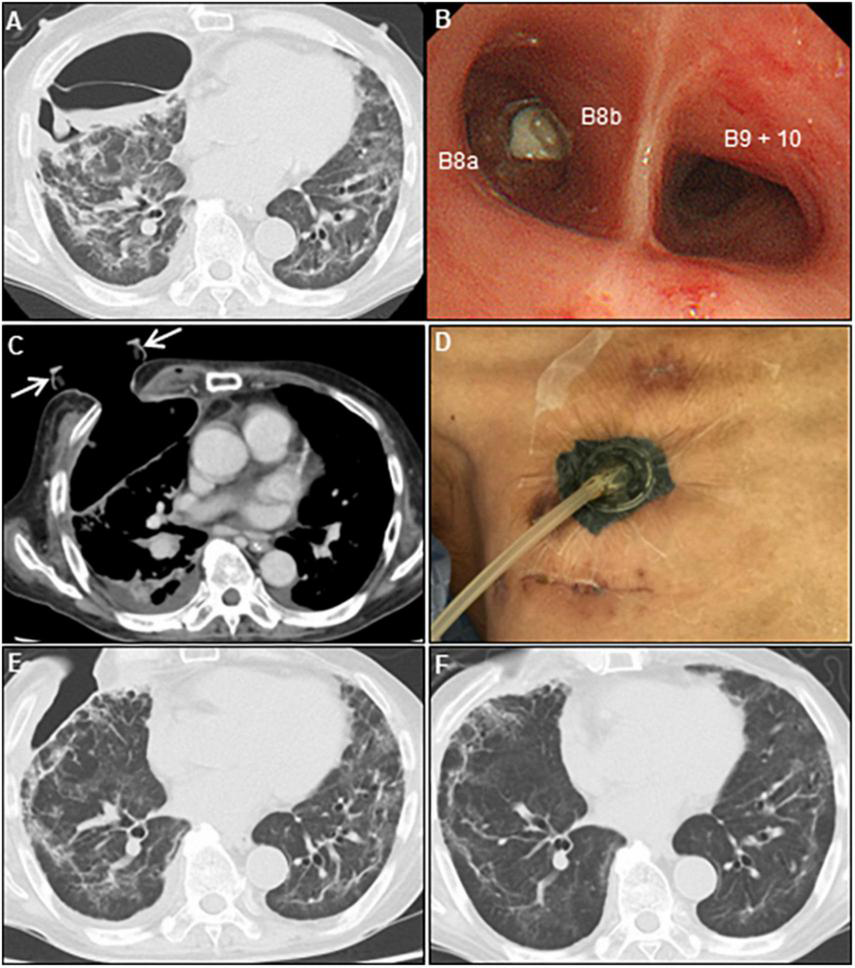

A 73-year-old man was admitted to our hospital for general fatigue, presenting with symptoms of productive cough and fever for 4 days. He was a former smoker who had smoked 20 cigarettes a day for 20 years but had no pre-existing lung disease. His vital signs were as follows: blood pressure, 115/80 mmHg; heart rate, 110 beats/min; blood temperature, 36.2°C; respiratory rate, 24 breaths/min; and oxygen saturation, 90% on ambient air. Hematological examination revealed the following: white blood cell count, 2,600 cells/μL; differential count, 65.5% neutrophils, and elevated levels of C-reactive protein, 5.13 mg/dL (normal < 0.14 mg/dL); D-dimer, 10.1 μg/mL (normal < 1.0 μg/mL); LDH, 384 U/L (normal range, 124–222 U/L); and serum ferritin, 1,776 ng/mL (normal range, 20–200 ng/mL). SARS-CoV-2 infection was confirmed through reverse-transcriptase polymerase chain reaction (RT-PCR). Chest computed tomography (CT) on admission revealed patchy ground-glass opacities in both peripheral lungs, indicative of interstitial pneumonia (Figure 1A). A monoclonal antibody therapy directed against the spike protein of SARS-CoV-2 (casirivimab–imdevimab, 600/600 mg as a single intravenous dose) was initiated for moderate COVID-19 pneumonia; however, it was ineffective. On day 3, the patient continued to worsen clinically with progressive ground-glass opacities observed on the follow-up chest CT (Figure 1B). Thus, oxygen was administered with a high-flow nasal cannula (HFNC) at 40 L/min, with FiO2 titrated for oxygenation. In addition, we used a combination of oral dexamethasone (6 mg daily for 10 day) and IV remdesivir (200 mg, followed by 100 mg daily for 5 day), together with tocilizumab infusion (480 mg daily for 1 day). The chest CT on day 7 of admission revealed extensive ground-glass opacities, and diffuse consolidation with air bronchogram showing anteroposterior gradient in both the lungs, consistent with that of ARDS (Figures 1C,D). The patient developed severe hypoxemia of SpO2 80%, despite HFNC oxygen therapy (FiO2 1.0, 40 L/min), requiring intubation for respiratory insufficiency and IMV in the intensive care unit. The PaO2/FiO2 ratio was 120, suggestive of moderate ARDS. The IMV in the prone position was applied at a tidal volume of 6.6 mL/kg, positive end-expiratory pressure of 15 cm H2O, plateau pressure of 14 cm H2O, and respiratory frequency of 28/min. On day 15, a catheter-related bloodstream infection caused by Enterobacter aerogenes led to bacterial septic shock, consequent acute kidney injury and disseminated intravascular coagulation, requiring vasopressors, continuous renal replacement therapy, steroid infusion (Solu-Medrol 40 mg, daily for 16 day), and heparin infusion for 7 day. In addition, broad-spectrum antimicrobial treatment with meropenem (1 g/day IV for 10 day) was initiated, followed by antimicrobial de-escalation based on antimicrobial susceptibility test results (ceftriaxone, 4 g/day IV for 12 day). The chest CT on day 22 of admission revealed several lung cysts related to diffuse alveolar damage, predominantly on the right lung. Note the air-filled cystic lesion communicating to the segmental bronchus, was suspicious of a bronchopleural fistula (BPF) (Figure 2A). Follow-up RT-PCR confirmed SARS-CoV-2 negativity. On day 26, since the patient’s clinical status gradually improved, he was weaned off the IMV and extubated. The patient’s clinical condition remained stable thereafter; however, consecutive chest CT scans revealed progressive increase in size and number of lung cysts with a tendency to fuse with each other (Figure 2B). Two days later, the patient presented with dyspnea and severe chest pain. His vital signs were as follows: blood pressure, 90/70 mmHg; heart rate, 124 beats/min; respiratory rate, 38 breaths/min; and oxygen saturation, 83% on ambient air. The breath sounds were significantly diminished on the right side. Chest CT revealed a large right pneumothorax due to collapsed cysts with mediastinal shift, strongly suggestive of tension pneumothorax (Figure 2C). Air leaks had persisted despite two consecutive 20-Fr chest drain insertions (Figure 2D). On day 53, autologous blood pleurodesis (ABP) procedure was performed (100 mL, twice), but PALs were still observed. Moreover, collected material from chest cavity drainage tube was purulent, and CT findings on day 70 of admission were consistent with those of empyema (Figure 3A). On day 76, we attempted to facilitate healing of the PALs by inserting an Endobronchial Watanabe Spigot (EWS), a type of silicone bronchial blocker. Leak isolation performed via sequential balloon occlusion of the segmental bronchus using a bronchoscope revealed that the main source of the PALs was located in the right B8b segment, which was confirmed by an immediate reduction in air leaks on deploying a medium-sized EWS (Novatech, La Ciotat, France), and the procedure was completed (Figure 3B). Although air leaks recurred after an hour, bronchoscopy did not show any displacement of the implanted EWS, suggesting that the PALs were presumably due to myriad alveolopleural fistulas (APFs). Subsequent thoracoscopy revealed that the empyema cavity was too narrow for thoracoscopic manipulation. Therefore, minimally invasive open-window thoracostomy (OWT) using a wound edge protector was performed to eliminate PALs (Figure 3C and Supplementary Figure 1A). The incision length was 7 cm and surgical time was 105 min. Nine days after a dressing change, we clinically confirmed the cessation of air leaks. On day 90, negative-pressure wound therapy (NPWT) with a vacuum-assisted closure (VAC) device (KCI Medical Products, Winborne, Dorset, United Kingdom) was performed (Figure 3D). The pleural cavity was filled with GranuFoam (VAC Granufoam; KCI Medical, San Antonio, TX, United States), and covered with semipermeable films. Continuous suction was initially started at a negative pressure of 50 mmHg, and then maintained at a maximum negative pressure of 125 mmHg, alongside careful monitoring of the lung tissue damage. The dressings were changed twice per week. The patient well-tolerated these serial procedures, and experienced relief from dyspnea. NPWT for 28 days allowed re-expansion of the collapsed lung and enhanced wound granulation, resulting in closure of the thoracic cavity without the need for muscular flaps (Figures 3E,F and Supplementary Figures 1B-E). The postoperative course was uneventful. However, on day 110, the patient developed an extrapulmonary complication of a subcortical hemorrhage of the right parietal lobe, for which endoscopic hematoma evacuation was performed on day 125. Eventually, the patient was transferred to another hospital for further rehabilitation on day 158. At the 1-year follow-up, no recurrence of pneumothorax was observed. We present a timeline of the case in Figure 4.

Figure 2. Serial chest CT images after induction of the invasive mechanical ventilation. (A) Axial chest CT on day 22 shows a lung cyst formation (red arrow) at the right S8 segment. Note the segmental bronchus connecting to the lung cyst (yellow arrowheads). (B) Chest CT on day 41 shows the gradually expanded cyst with air-fluid level, and wall thickening secondary to lung suppuration (red arrow). (C) Chest CT on day 43 shows a huge right-sided pneumothorax with mediastinal shift (yellow arrowheads). Note the collapsed cyst in the right segment 8 (red arrow). (D) Chest CT on day 51 shows residual air leaks after chest tube drainage (white dotted arrow), extending massive subcutaneous emphysema, and further enlargement of other lung cysts (white arrowheads). CT, computed tomography.

Figure 3. Multidisciplinary approach for persistent air leaks. (A) Chest CT on day 70 shows empyema and dense pleural thickening with air-fluid level. (B) Bronchoscope shows an endobronchial valve deployment inserted into the right B8b segment. (C) Post-minimally invasive OWT using a wound retractor (white arrows). (D) VAC system. Chest CT on day 97 (E) and 143 (F) show re-expansion of the collapsed lung parenchyma, and a repair of the chest wall after VAC therapy. CT, computed tomography; OWT, open-window thoracostomy; VAC, vacuum-assisted closure.